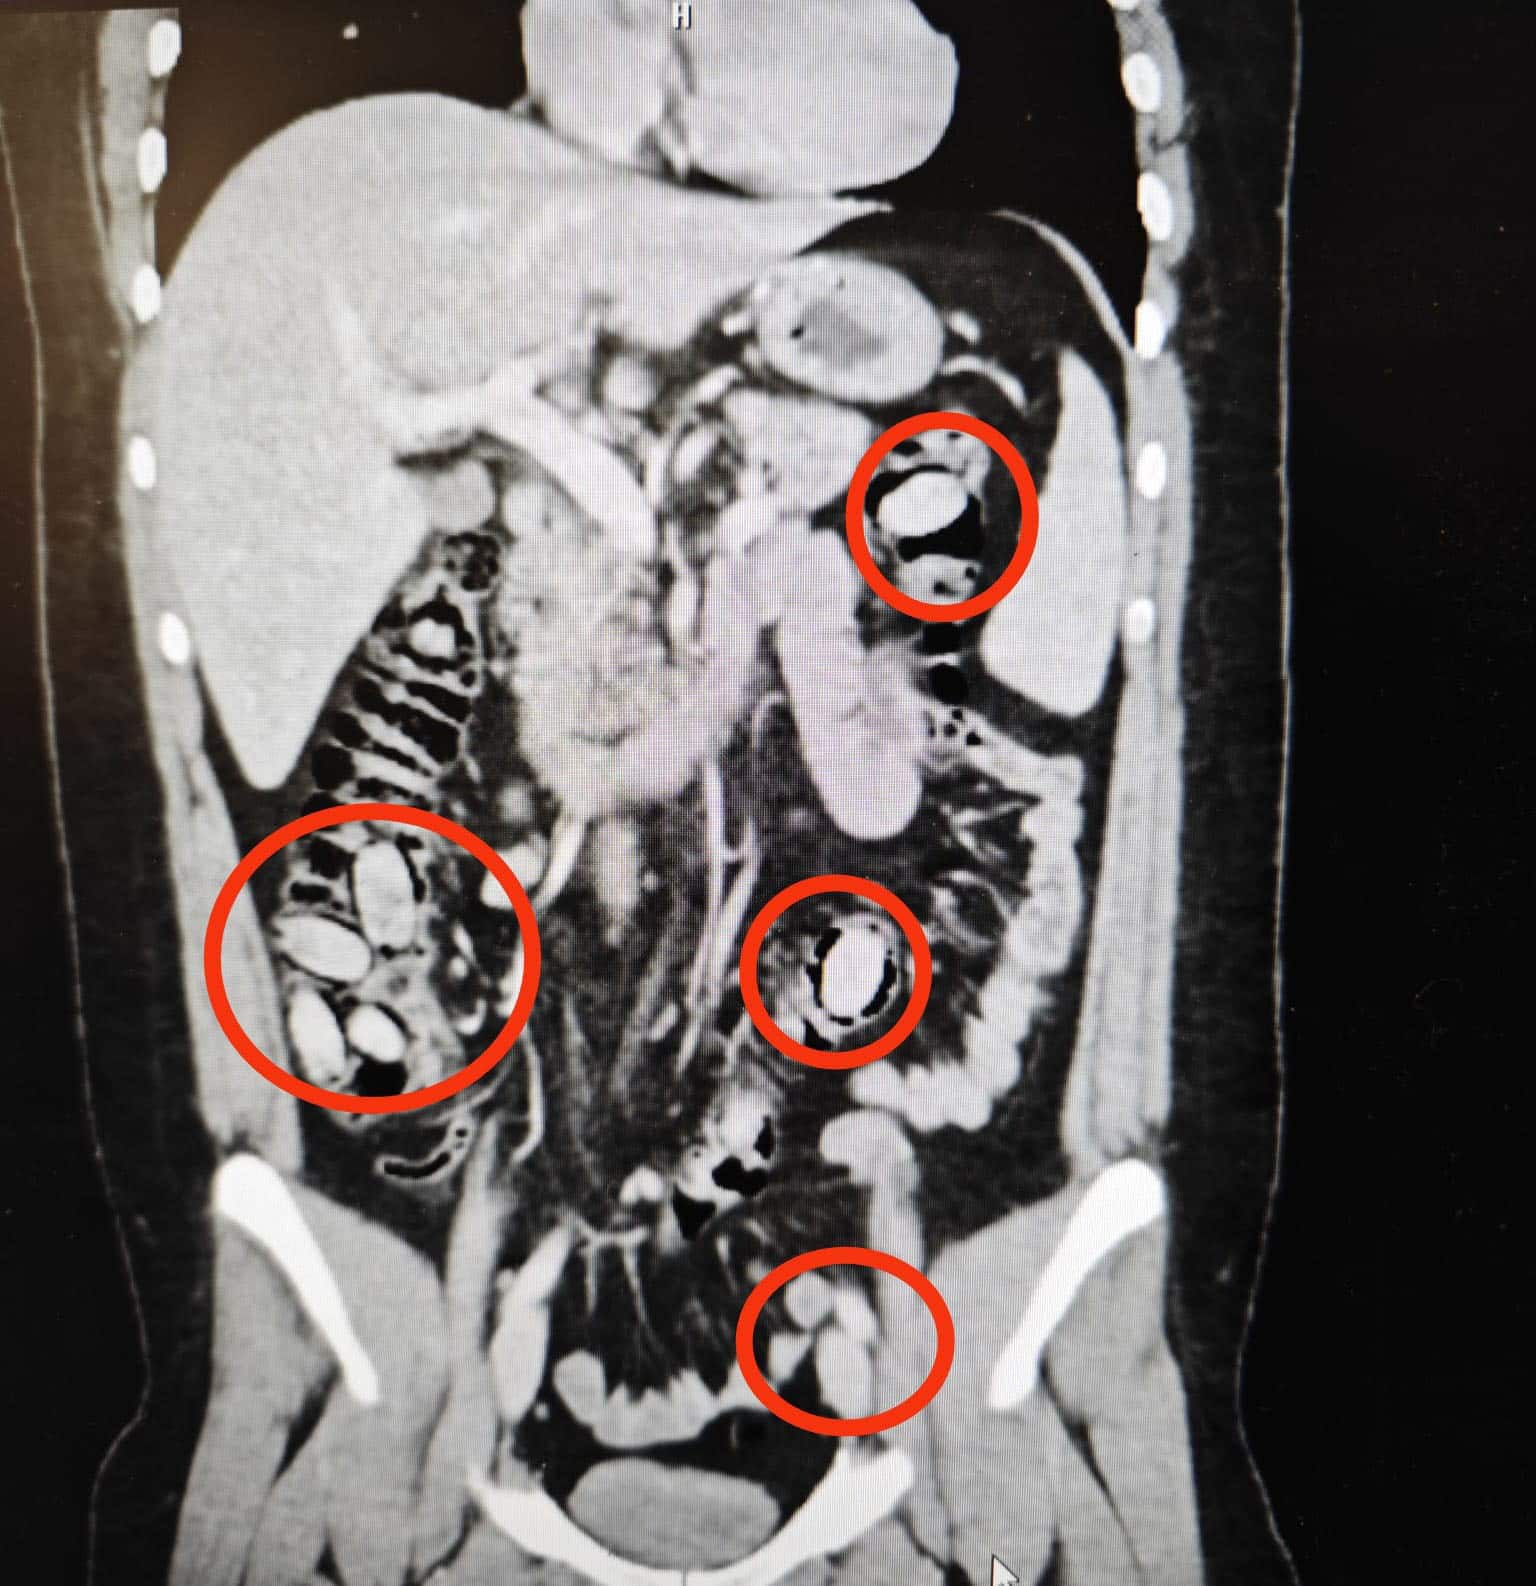

Sürekli midesini tutmasından şüphe edilmesi üzerine S.A., hastanede sağlık kontrolünden geçirildi. Şüpheli S.A.’nın hastanede çekilen röntgeninde midesinde 44 kapsül olduğu tespit edildi.

Eskişehir Cumhuriyet Başsavcılığı’nın talimatıyla cerrahi müdahaleye alınan S.A.’nın midesindeki 44 kapsül çıkarıldı.

Kapsüllerde yapılan incelemede içerisinde uyuşturucu metamfetamin (bonzai) maddesi olduğu belirlendi.